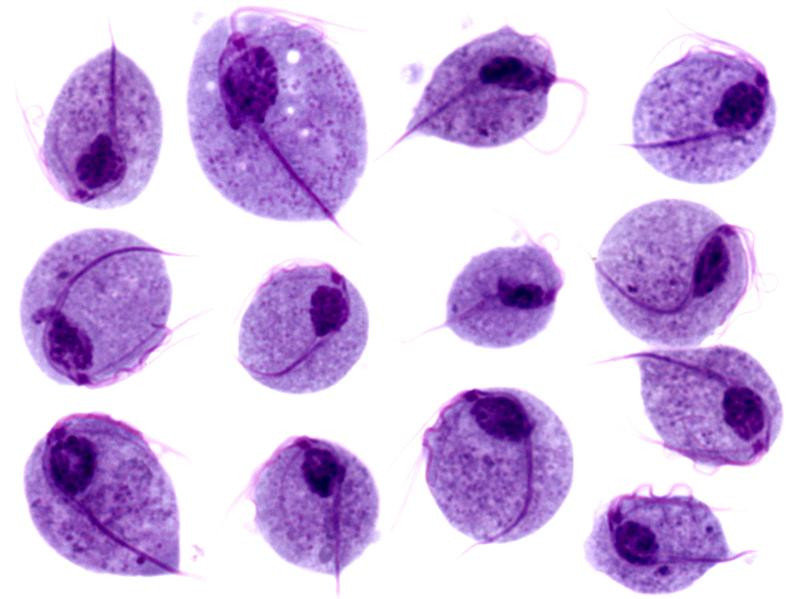

WHAT IS TRICHOMONAS?Trichomonas is a small, single-celled organism, larger than a bacterium, that can move by means of moving parts. Under a microscope, they can be seen swimming by at considerable speed. They are common, worldwide. They don't cause many symptoms: in women, they can cause increased vaginal discharge (vaginal discharge), sometimes with a foul odor. It is easily treated with antibiotics.

![Trichomonas vaginalis, trichomoniasis (click on photo to enlarge) [source: Texas Tech University Health Sciences Center (TTUHSC) - www.ttuhsc.edu] Trichomonas vaginalis, trichomoniasis](../../images/soa/trichomonas-vaginalis-3z.jpg) |

Trichomonas vaginalis |

Photos: Texas Tech University Health Sciences Center and isis325 - Wikimedia (Creative Commons License 2.0 ).